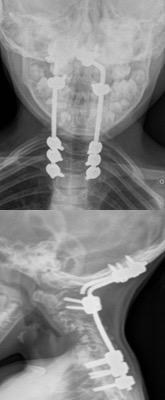

- Figura 8. Radiografías cervical AP y Lateral

- Figura 7. Radiografías Post revisión AP y Lateral